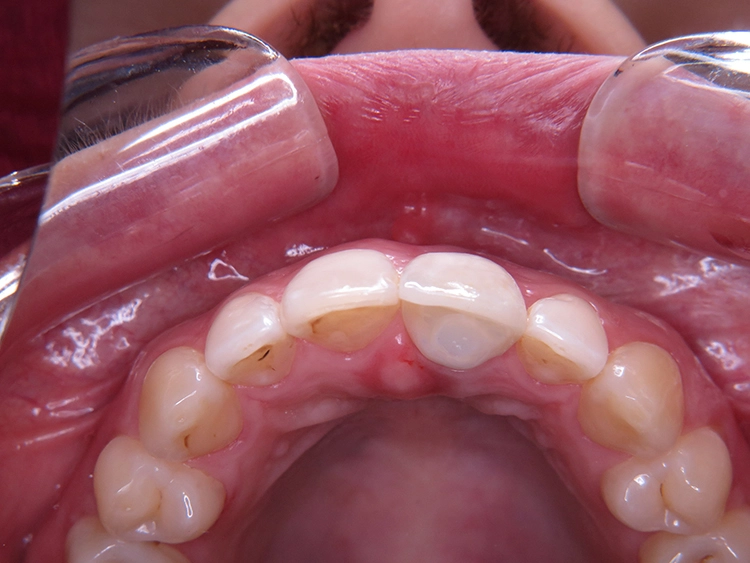

Die junge Patientin konsultierte die Zahnarztpraxis mit Beschwerden am Zahn 21. Der endodontisch vorbehandelte Zahn (multiple Wurzelspitzenresektionen) war mit einer Krone prothetisch versorgt (Abb. 1). Die Krone wirkte im Mund etwas dunkel und hatte einen grauen Schimmer. Da der Zahn zudem immer wieder Beschwerden bereitete, äußerte die Patientin den Wunsch nach einer Neuversorgung. Ansonsten war sie vollbezahnt und funktionell ohne pathologischen Befund. Parodontal zeigte sich eine kleine Rezession im Unterkiefer-Frontzahnbereich.

Zu den schwierigen Anforderungen im Frontzahnbereich gesellten sich hohe ästhetische Ansprüche. Die klinische sowie radiologische Diagnostik (Abb. 2) ergaben, dass der Versuch des Erhalts von Zahn 21 keine sichere Perspektive bot. Die Entscheidung fiel für die Extraktion des Zahnes. Um das Hart- und Weichgewebe bestmöglich vor der physiologischen Remodellierung nach der Extraktion zu bewahren, wurde eine Sofortimplantation geplant.